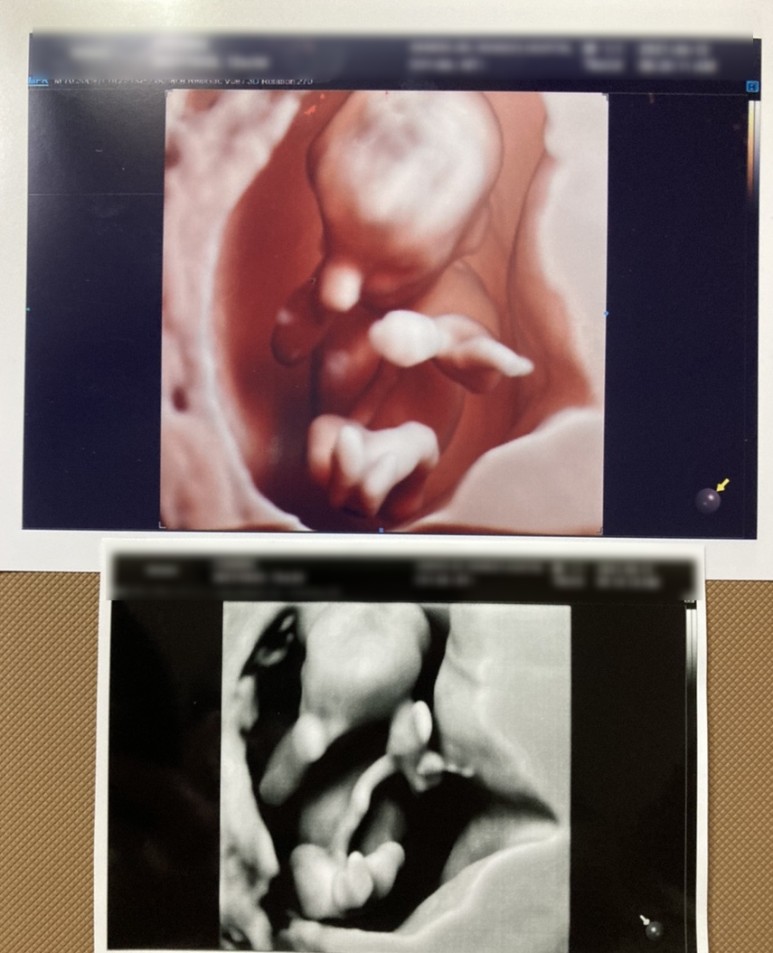

왼쪽사진은 한방을 밑에서 찍은모습이고 궁에들어와 양다리www11주차가 된 한방은 이미 꽤 사람같았다. 그리고 이날 초음파를 봤는데, 아무리 움직여도, 아기 집을 팡팡 발로 차고, 손도 엉망진창이여서, 너무 귀여웠다. 벌써부터 도치맘…?